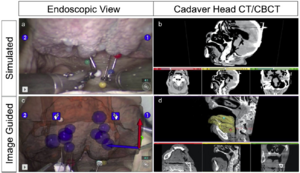

Low-cost Interactive Image-based Virtual Endoscopy for the Diagnosis and Surgical Planning of Suprasellar Arachnoid Cysts

Publication: World Neurosurg. 2015 Dec 27. PMID: 26732948

Institution: Department of Neurosurgery, People's Liberation Army General Hospital, Beijing, China. Background/Purpose: OBJECTIVE: To investigate the feasibility and reliability of virtual endoscopy (VE) as a rapid, low-cost and interactive tool for suprasellar arachnoid cysts (SACs) diagnosis and surgical planning. Methods: 18 SACs patients treated with endoscopic ventriculocystostomy were recruited, and same number of endoscopic third ventriculostomy treated patients was randomly selected as VE reconstruction control group. After loading their DICOM data into free software 3D Slicer, VE reconstruction was independently performed by 3 blinded clinicians and the time required for each reconstruction was recorded. Other 3 blinded senior neurosurgeons interactively graded the visibility of VE by watching video recordings of endoscopic procedures. Based on the visibility scores, Receiver Operating Characteristic (ROC) curve analysis was used to investigate the reliability of VE to diagnose SACs, and the Bland-Altman plot was employed to assess the VE's reliability for surgical planning. In addition, intra-class correlation coefficient (ICC) was calculated to estimate the consistency among the results of 3 reconstructing performers. Results: All 3 independent reconstructing performers successfully completed VE simulation for all cases, and the average reconstructing time was 10.2±9.7 minutes. The area under ROC curve of cyst's visibility score was 0.96, implying its diagnostic value of SACs. Bland-Altman plot indicated good agreement between VE and intraoperative viewings, suggesting the VE's anatomical accuracy for surgical planning. In addition, ICC was 0.81, which revealed excellent inter-performer consistency of our simulation method. Conclusion: This study substantiated the feasibility and reliability of VE as a rapid, low-cost and interactive modality for SACs diagnosis and surgical planning. |